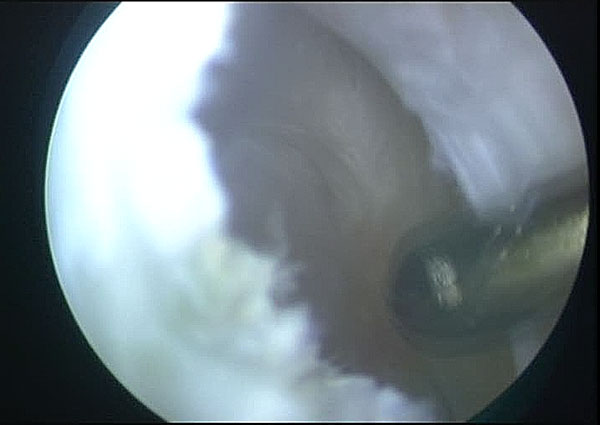

Arthroscopic Management of Baker's CYST